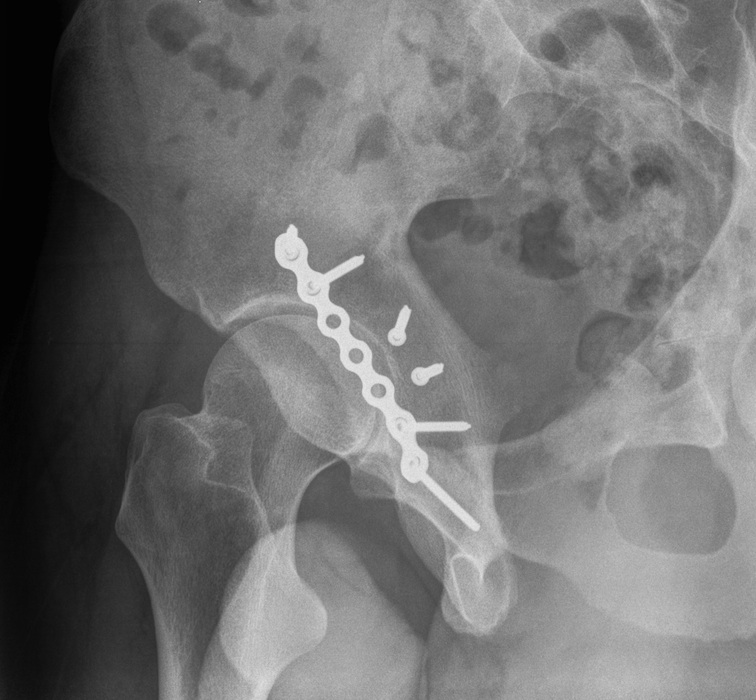

Anterior Column & Wall Fracture

ORIF

1. Reduce quadrilateral plate

- small T plate / will sit under pelvic reconstruction plate

- separate recon plate

2. Plate iliac crest fracture

- long 13 hole plate from pubis

- along superior pubic ramus up onto inner table of ilium

- indirect acetabular reduction